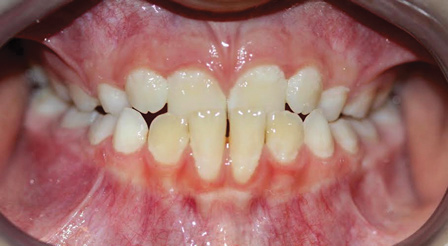

Dental impactions may occur for several reasons. A common occurrence is insufficient arch length leading to crowding. Another potential reason is early loss of primary teeth without proper space maintenance, allowing the permanent dentition to drift mesially and block out the primary tooth's successor. Maxillary canines are the most commonly impacted teeth besides third molars. These teeth have the longest path of eruption, are one of the last teeth to erupt into the mouth, easily become blocked out due to crowding or trauma history, and have a genetic component to being palatally impacted.5,6 Early signs of canine impaction may be severe crowding and the permanent lateral incisor crowns flaring distally. The crown of the impacted canine, in essence, is applying pressure to the roots of the lateral incisors in these instances (Figure 3 and Figure 4).

Fig 3. Impacted canine, dentofacial signs.

Figure 3